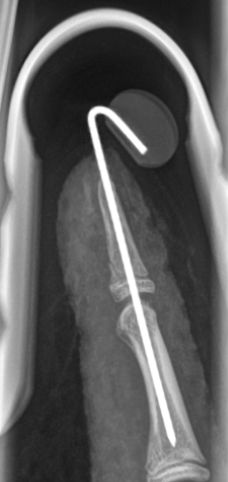

- Seymourfraktur - dislocerad Salter-Harris typ I eller II med luxerad nagel där nagelmatrix ligger interponerad i frakturen:

- Behandlas som öppen fraktur

- Antibiotika i.v.

- Snar öppen operation (inom 24 timmar) där man:

- reponerar interponat

- reponerar frakturen

- suturerar nagelanlaget

- fixerar frakturen med längsgående stift förbi DIP-led

Seymour-fraktur innan, under och efter operation